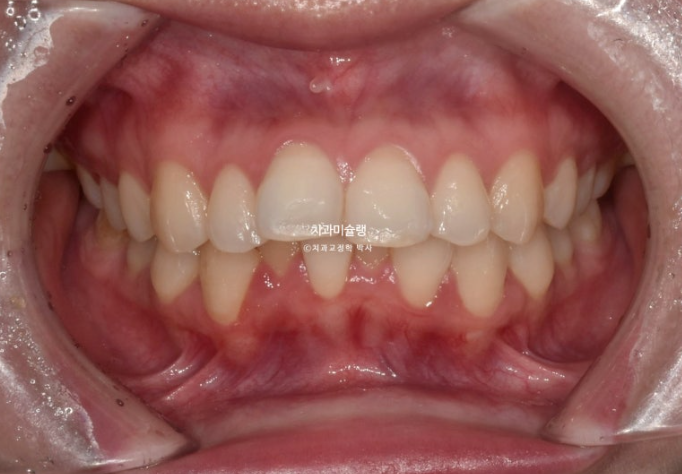

위 아래 중심선은 어긋나 있고

윗니가 아랫니를 많이 덮어 아랫니가 잘 안보이는 심한 과개교합이 보입니다.

어긋나 있던 중심선은 정확히 맞으며 깊게 물리는 과개교합이 해소되어 이제 아래 앞니가 정상적으로 보입니다.

뿐만 아니라 치아 높낮이 불규칙으로 인해 들쑥날쑥 했던 아래 앞니가 배열되면서 잇몸라인도 어느정도 정리가 되었습니다.